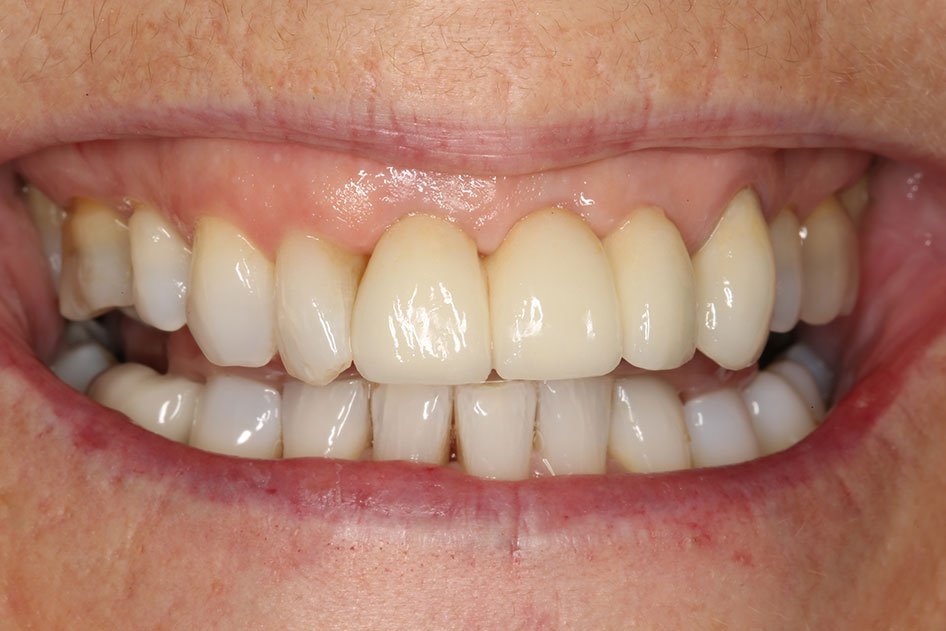

The implant crown is supported by the implant fixture. It is carefully crafted to look and feel like a healthy, natural tooth.

Dental implants have a number of advantages over more conventional methods of replacing missing teeth. An implant-supported crown is very similar to your natural tooth because it is fixed permanently, and does not need your other teeth or soft tissues for support.